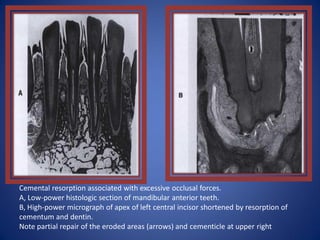

Cemental resorption associated with excessive occlusal forces.

A, Low-power histologic section of mandibular anterior teeth.

B, High-power micrograph of apex of left central incisor shortened by resorption of

cementum and dentin.

Note partial repair of the eroded areas (arrows) and cementicle at upper right